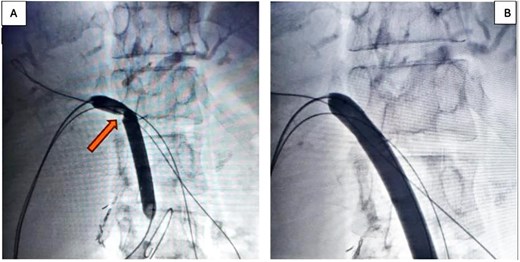

In the stage 2 procedure (15 days later), Spyglass Discover cholangioscopy was performed using the matured tract. Cholangiography was performed through the catheter, identifying the persistence of intrahepatic stones. The catheter was removed, and using the Seldinger technique, the fistulous tract was progressively dilated to 13 Fr to place an 11/13 Fr Navigator introducer. Through this, the single-operator Spyglass Discover - Boston Scientific choledochoscope was advanced, navigating toward the right and left main hepatic branches. Electrohydraulic lithotripsy (EHL) was applied to the stones, completely fragmenting them. Subsequently, endoluminal plasty of the anastomosis was performed with a 10 × 60 mm balloon (Fig. 2A and 2B), and a 10 × 57 mm biodegradable stent was implanted. Irrigation is then performed with 300 milliliters of saline solution to sweep the stone fragments toward the jejunal loop. The final cholangiography demonstrated adequate contrast flow throughout the right and left biliary trees and toward the loop (Fig. 3A). An 8 Fr feeding tube was left in segment VI to secure the path in case of complications with the stent and was left connected to a free-fall collection bag. Total procedure time was 180 minutes.

(A) Pre-removal cholangiography of a Nelathon catheter placed in the peripheral branch of segment VI to ensure the path in case of complications, showing fluid passage toward the efferent loop; (B) 3D tomographic reconstruction allows a 360-degree view of the passage of contrast throughout the biliary tree.

The patient recovered uneventfully. A control cholangiography with 3D tomographic biliary reconstruction was performed, demonstrating adequate functioning of the stent (Fig. 3B); therefore, it was decided to remove the catheter from the fistulous tract to allow spontaneous closure by secondary intention. The patient had a 24-hour hospital stay. At control, 30 days post-procedure, normalization of the cytolytic profile was observed: TB: 0.98, DB: 0.89, patient asymptomatic.